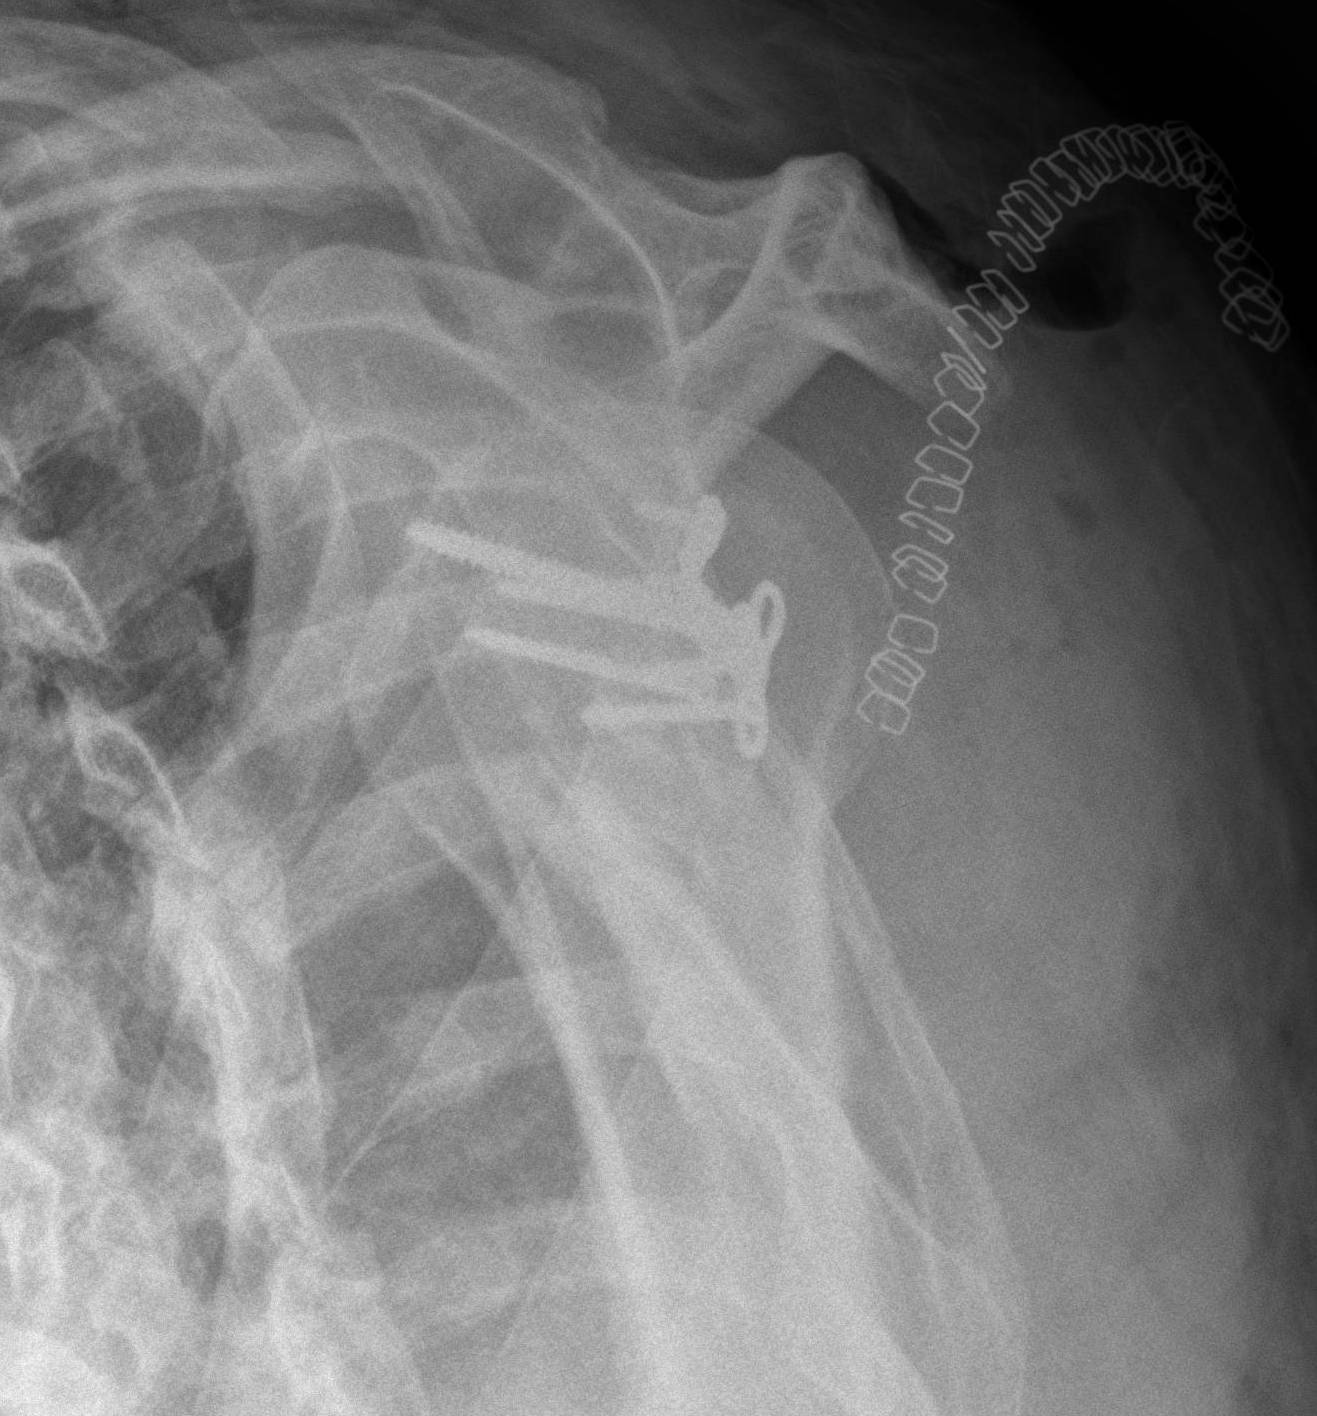

Case 2

Type II

Transverse fracture through glenoid fossa

- inferior triangular fragment

- exits lateral border scapula